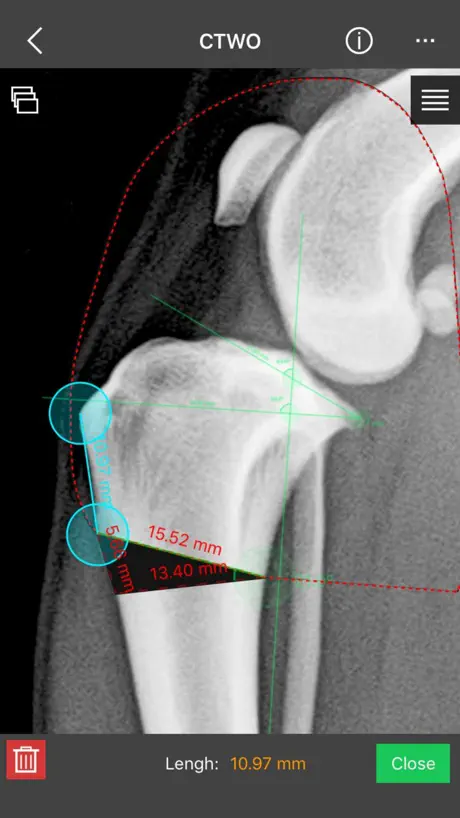

This is a useful tool for traumatology and orthopaedic surgical planning veterinary, including advanced techniques for treat canine anterior cruciate ligament (ACL) injuries (TPLO and CTWO).

a) Linear Measure.

b) Radial measure/Circle draw.

c) Angle measure/Triangle draw.

e) Wedge cut, CTWO and angular osteotomies.

This is a useful tool for traumatology and orthopaedic surgical planning veterinary, including advanced techniques for treat canine anterior cruciate ligament (ACL) injuries (TPLO and CTWO).

a) Linear Measure.

b) Radial measure/Circle draw.

c) Angle measure/Triangle draw.

e) Wedge cut, CTWO and angular osteotomies.